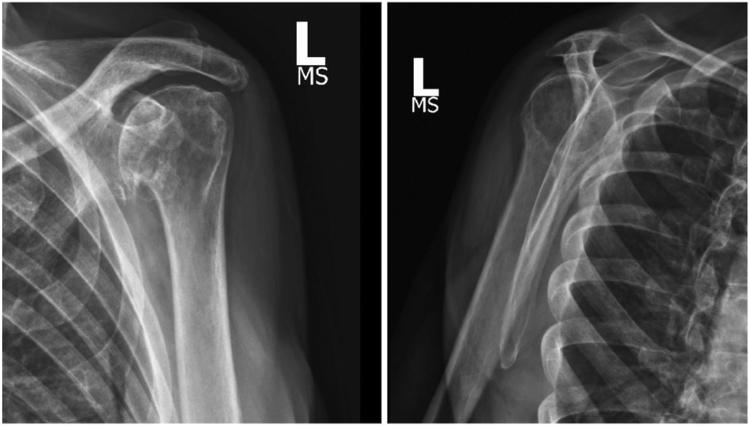

Survival of humeral head autograft for glenoid bone loss in reverse total shoulder arthroplasty: a case report of long-term follow-up post ground level fall.

Survival of humeral head autograft for glenoid bone loss in reverse total shoulder arthroplasty: a case report of long-term follow-up post ground level fall.自体肱骨头移植治疗反式全肩关节置换术中肩胛盂骨缺损的生存情况:平地跌倒后长期随访的病例报告